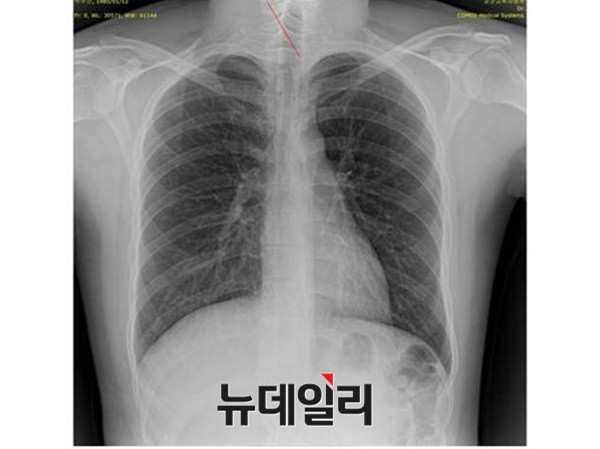

2011년 박주신씨에 대한 병역비리 의혹이 처음 불거진 뒤 지금까지 박주신씨의 신체를 촬영한 것으로 알려진 엑스레이는 모두 3개가 있다.이 가운데 언론을 통해 널리 알려진 자생병원 엑스레이(촬영일자 2011년 12월 9일)는, 박주신씨 본인이 아닌 제3자의 신체를 촬영한, 이른바 ‘대리신검자 엑스레이’라는 의심을 받고 있다.

- ▲ 박주신씨 명의의 자생병원 엑스레이. ⓒ 뉴데일리DB

반면 지난해 12월부터 시작된 양승오 박사 등 시민 7명에 대한 공직선거법 위한 공판을 통해 새롭게 밝혀진, 박주신씨의 ‘공군훈련소 입소 당시 엑스레이’(촬영일자 2011년 8월 30일, 이하 공군 엑스레이)와, 주신씨가 ‘비자발급을 위해 촬영한 세브란스병원 엑스레이’(촬영일자 2014년 7월 31일, 이하 비자발급용 엑스레이)는 각각 박주신씨 본인의 신체를 촬영한 것으로 받아들여지고 있다.

- ▲ 박주신씨 공군훈련소 입소 당시 촬영된 엑스레이. ⓒ 뉴데일리DB

- ▲ 박주신씨가 지난해 7월 비자발급을 위해 촬영한 엑스레이. ⓒ 뉴데일리DB

이들 세 개의 엑스레이는 모두 박주신씨의 신체를 촬영한 것으로 알려져 있기 때문에, 이들 엑스레이에 대한 판독결과 피사체를 동일인으로 볼 수 없는 유의미한 차이점이 발견된다면, 이는 박주신씨의 대리신검 혹은 영상자료 바꿔치기 의혹을 뒷받침하는 결정적 단서가 된다.

세계적 권위를 인정받은 영상의학 전문의인 양승오 박사(동남권원자력의학원 암센터 핵의학과 주임과장)와 치과의사 김우현씨 등 박주신씨 병역비리 의혹을 주장해 온 시민들은, 위에서 언급한 세 개의 엑스레이에 대한 비교 판독 결과, 이들 엑스레이를 같은 사람의 것으로 볼 수 없는 차이점을 발견하고 이를 재판부에 증거자료로 제출했다.

‘석회화’란 나이가 들어 뼈에 발생하는 퇴행성 증상의 하나로 질병이라고 볼 수는 없지만 한 번 생기면 없어지지 않으며, X-Ray를 통해 확인할 수 있는 것으로 알려졌다.

- ▲ ▲박주신의 자생병원 X-Ray(왼쪽)과 공군 X-Ray(오른쪽). 자생병원의 엑스레이에서는 오른쪽 제1늑골부위에 '석회화'현상이 보이지만 공군엑스레이에선 보이지 않는다. ⓒ 뉴데일리DB

박주신씨의 자생병원 X-Ray를 보면, 오른쪽 제1 늑골부위에 ‘석회화’ 현상이 나타난다. 그러나 주신씨가 공군 입대 당시 찍은 X-Ray에는 이런 모습이 전혀 보이지 않는다.

이런 차이에 대해 양승오 박사의 변호인인 차기환 변호사 등은 "각각의 X-Ray를 찍은 사람이 동일인이 아니라는 것을 입증한다"고 설명했다.

‘극상돌기’의 경우에도 차이점은 명확히 드러난다.

변호인 측은 “공군에서 찍은 엑스레이와 비자발급을 위해 찍은 엑스레이에서는 피사체의 제 1흉추 극상돌기가 오른쪽으로 휘어있지만, 자생병원에서 찍은 영상에서는 정방향으로 나온다”며, “박주신씨가 공군에 입대해 찍은 엑스레이와 세브란스 공개신검에서 나타난 피사체의 의학적 차이가 명확해 동일인이라고 인정할 수 없다”고 지적했다.

우리가 흔히 등을 만지면, 가운데 뾰족하게 솟아난 부분이 바로 ‘극상돌기’다.

흉추를 비롯해 모든 척추에 존재하며, 흉추에 외상이나 수술, 질병 등이 없었던 근접한 기간 동안 촬영된 엑스레이에서 극상돌기의 형태가 명확하게 다를 경우, 다른 개체라고 판단할 의학적 근거가 된다.